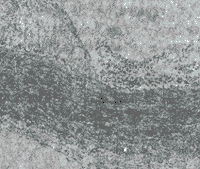

实验组家兔8只的血管内膜均可见不同程度的淡黄色斑块,以主动脉弓、腹主动脉及肾主动脉分叉处较明显,脂肪染色显出明确的红色斑块,组织切片HE染色,动脉内膜弥漫增厚,有的呈丘状突向管腔,内膜下有较多泡沫细胞和少量成纤维细胞及胶原(图1)。冠状动脉和心肌内血管内膜增厚更严重并纤维化、玻璃样变、管腔闭塞(图2)。实验组大鼠20只和所有对照组家兔及大鼠的冠状血管及主动脉等的内膜光滑、未见明显异常,脂肪染色阴性,HE染色动脉各层结构清楚完好。

Fig 1 The AS plaque of aorta abdominalis of rabbit after 42 d with hypercholesterol feeding,The plaque had essentially monocytes/macrophages\foam cells and fibroblasts under intimal membrane,and protruded to lumen of the vellel.HE 12.6×10

图1 高脂饲料喂养42 d后家兔腹主动脉内膜的AS斑块